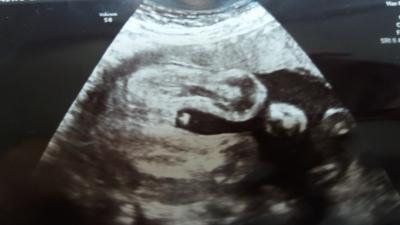

hallo!! ich brauche eure hilfe, bin jetzt in der 25ssw, in der 16 ssw hab ich ein 60% outing zum Jungen gekrigt und gestern sieht eher nach einem jungen aus, wie war es bei euch? hab auch ein bild hoch geladen, was meint ihr kann ich mir sicher sein dass es ein junge ist?

Bild zu junge?? - Schwanger - wer noch? Rund um die Schwangerschaft

Am Bild kann man es finde ich nicht richtig erkennen- wenn der Arzt einen jungen vermutet, dann soll der weiße Fleck vor den Beinen wohl der Hoden sein und man kann gaaaanz leicht angedeutet den schnippi erkennen. Aber, es könnte genauso die NS sein. Das Bild ist nicht ganz gelungen- um jetzt eindeutig sein zu können.

Sieht für mich nach Mädel aus :)

Ich hab einen Jungen und bekomme in 3 Wochen ein Mädchen. Bei meinem Sohn war es sehr eindeutig. Hier ist es schwer zu erkennen, aber ich würde ganz vorsichtig auf ein Mädchen tippen. Mit dem shoppen würde ich allerdings noch warten.

Hi, ich denke das ist die Nabelschnur... Und das davor die Schamlippen

sieht für mich deutlich aus wie ein Junge. Ich gab 2 und das sah damals genauso aus